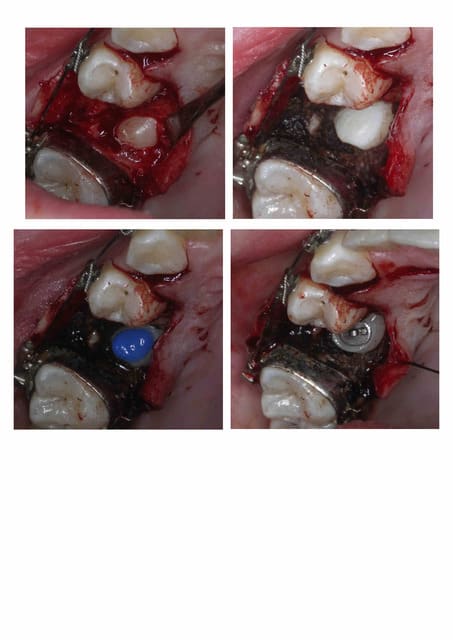

le problème étant le séchage du champ opératoire, j'arrête le saignement avec de l'Astrigedent (FeSO4 à 15,5 % préparé par le pharmacien)(photo en haut à droite), ensuite c'est simple mordançage + Optibond + Tetric sur le bouton.

Le dégagement osseux n'est pas forcément énorme, il suffit de faire la place pour coller le bracket.

J'utilise des compos et bonding de collage pour orthodontiste. Il y a plus de 20 ans j'ai commencé avec du superbond, les compos et bonding de l'époque ne tenaient pas. Du coup il fallait rester au sec le tps de prise... :(

La photo d'intervention ne correspond pas au cas "développé" mais était très similaire.